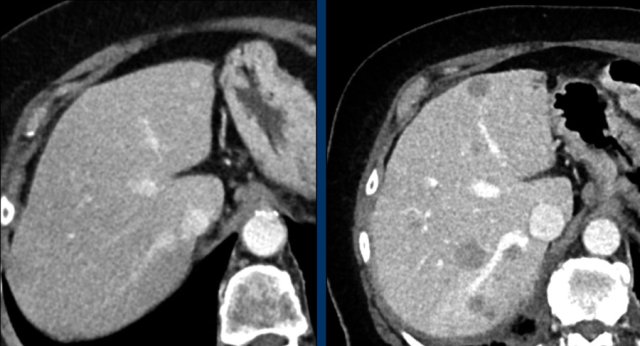

The CT images of a 82-year-old male show liver metastases of a GIST at baseline (arrowheads).

All metastases decrease somewhat in size after treatment with imatinib, but the most remarkable difference is a decrease in density.

This is considered to be a good response according to the Choi criteria.